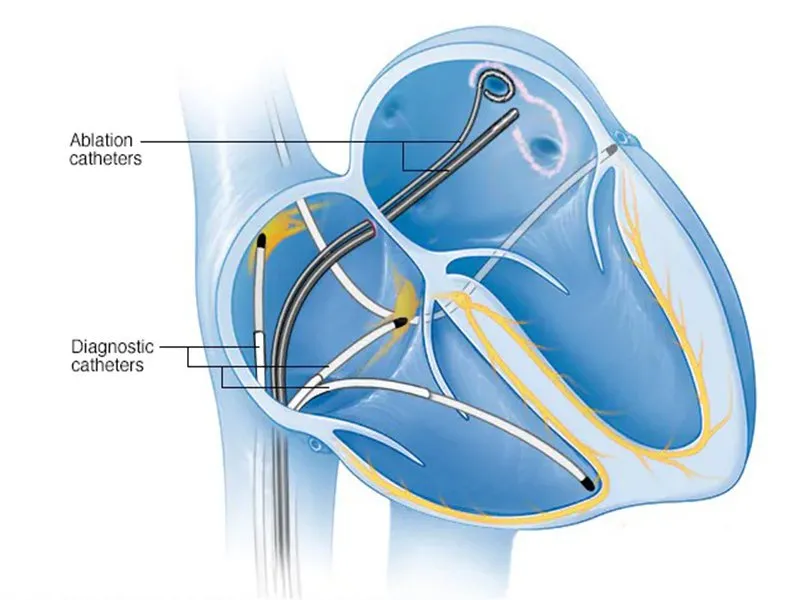

Cắt đốt bằng ống thông (Cardiac Ablation) là thủ thuật điều trị rối loạn nhịp tim bằng cách tạo sẹo hoặc phá hủy mô tim bất thường. Ống thông được đưa vào tim qua tĩnh mạch/động mạch để đốt các mô...

Cắt đốt bằng ống thông (Cardiac Ablation) là thủ thuật điều trị rối loạn nhịp tim bằng cách tạo sẹo hoặc phá hủy mô tim bất thường. Ống thông được đưa vào tim qua tĩnh mạch/động mạch để đốt các mô...